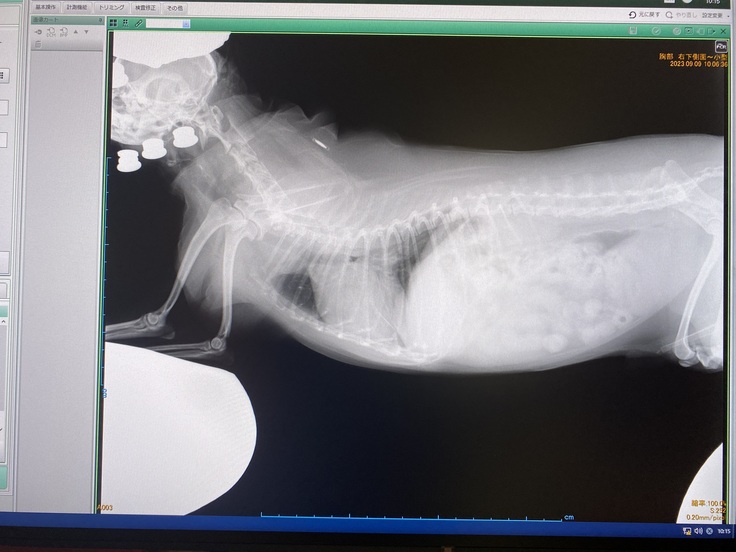

取り急ぎInstagramでご報告させていただいておりましたが、昨夜から舌をペチャペチャとする行動や細かい回数の多い咳が多かった為、今朝病院に連れていき、レントゲンと血液検査をしてきました。

結果は肺ではなく今度は胸水が溜まり始めていると言われました。

溜まっている場所は肺の中ではなく外側に位置する場所?らしいです。

肺水腫の場合は肺の中がスポンジが水を吸収していくように溜まっていくと先生は表現しておりました。

胸水が溜まると肺の外側からも水が溜まり、それが大きくなると更に肺を圧迫してしまい、息が苦しくなってしまったり、食欲が低下してしまうようです。

今は肺炎を引き起こしている状況のようです。